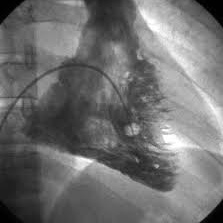

Ventriculografia de ventriculo derecho. 920403 Idime (2024)

IDIME. Instituto de Diagnóstico Médico. Código de Convenio : 8915

BOGOTÁ

Sede calle 77: Calle 77 No. 23 -35

Sede Occidente: Av. de la Américas No. 69 C 94

INCLUYE UNIDOSIS TECNECIO, Y PIROFOSFATO ESTAÑOSO